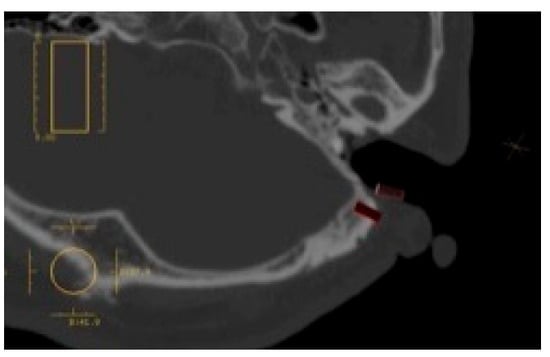

In surgery planning, clinical anatomy-based selection of the location for implant placement is critical. First, during the facial observations, verify the distance between the outer canthus and the tragus (Figure 1), as well as whether the angle of the naso-auditory meatus line is symmetrical in relation to the bipupillar line. In most cases, they are symmetrical, and the location of the epithesis would be considered in such a way that the epithesis appears symmetrical in relation to the unaffected ear in both its placement and form. It is easiest to get a visual image by using mirroring technologies in stereolithography, by casting, or if an inverted model is created and prepared from the unaffected auricular based on the earlier wax-up (Figure 2). However, it is possible that the actual epithesis turns out to be asymmetrical in location, form, or color. It is important to sufficiently inform the patient and their family about the limitations of the treatment and obtain their consent. The implant site must be chosen so that perforation of the cavernous sinus and facial nerves does not occur (Figure 3); thus, the method of Tjellström et al. should be followed [2], as it considers the position of the epithesis based on its mechanical and aesthetic properties. In other words, this is a method that considers a safe implant site to be the site where the following is taken into consideration: the reference axis is set based on the straight line that connects the outer canthus and the tragus in the 3:00 to 9:00 direction of a clock, and a straight line that perpendicularly crosses the previous line centering the external auditory canal in the 0:00 to 6:00 direction also: if the right side is the affected side, the 7:30 to 8:30 and the 10:00 to 11:00 directions along with the location would form an antihelix. As the antihelix is located approximately 20 mm from the external auditory canal, during the operation, there will be a total of two implants: one implant in the 7:30 to 8:30 direction and the other in the 10:00 to 11:00 direction at a distance of approximately 20 mm away from the external auditory canal (Figure 4). While considering the above basics, the clinician would need to decide on the actual implant site based on clinical observations and findings from a CT scan. Next, the distance between the bone surface to the inside of the cranium is calculated using the CT images and models. Keep in mind that 4 to 8 mm implant bodies will be inserted from the temporal bone surface, the drill length is slightly longer than the implants themselves, and there is a chance that a technical error could cause the drill to go slightly deeper than intended. It would therefore be advisable to ensure the implant has at least 2 mm clearance to the inside of the cranium.

Figure 8. CT image after implant placement.